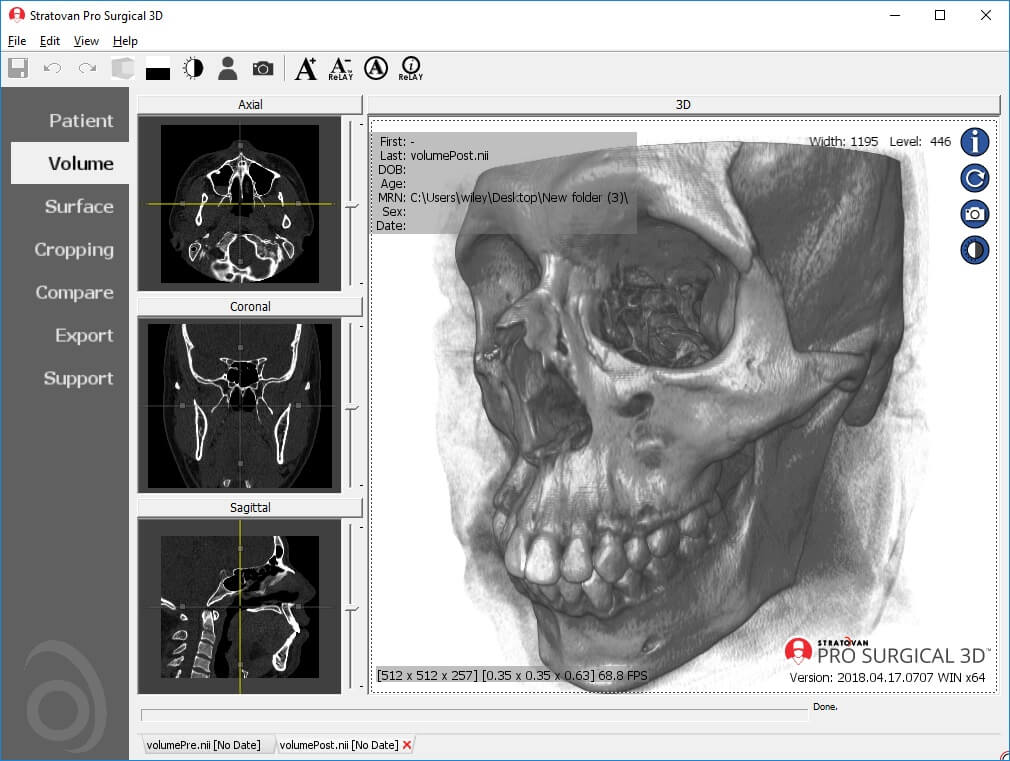

The Pro Surgical 3D application (from the Stratovan Group) is mainly targeted at surgeons, for surgical planning using their high quality 3D reconstruction feature. However, anyone can use this application to read and understand scans. It has the capacity to anonymize and de-identify patient details in scans, which is a must when the images are used in research, presentations or publications. They have an integrated customer support portal to aid in usage. The application also provides access to the Navegatium Knowledge Base—a comprehensive digital library of medical images.

Some drawbacks are that it occupies a lot of hard disk space, requires an advanced version of Windows (at least Windows 8.1 or 10) and high-speed RAM.

| 5. | Pro Surgical 3D | Windows 8.1 or higher | Not available | Y | Y | N | STL and PLY formats | 1 GB | Intel i3/ 8+ GB RAM; 1920x1080 | Freeware |